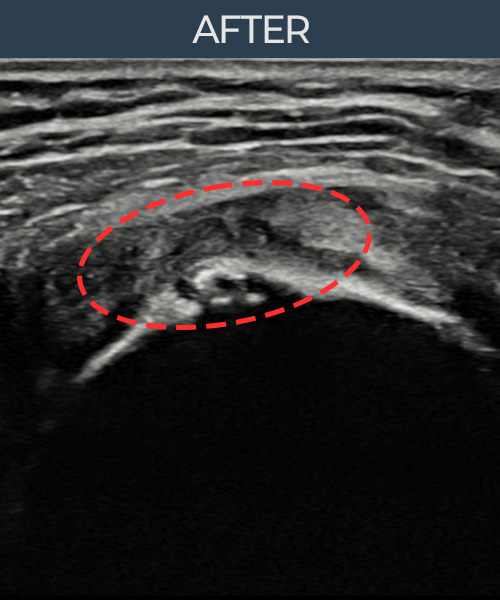

비수술 치료 전후사진

비수술로도 파열된 인대를

물리적으로 재건해 드립니다

인대강화주사만으로는 해결되지 않던 인대파열.

플래티넘정형외과에서는 수술없이도 물리적으로

파열된 인대를 재건

하는것이 가능합니다.